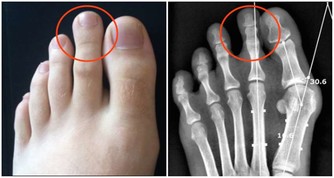

食物消化後的殘渣也要通過腸道排泄出去,如果這些垃圾堆積在體內不及時排出去,就會產生很多有害物質,引起腹漲、腹痛,甚至引起腸道擴張、誘發腫瘤。